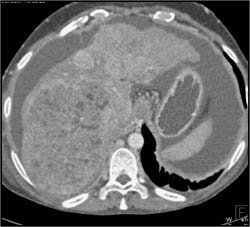

Hepatoma With Neovascularity